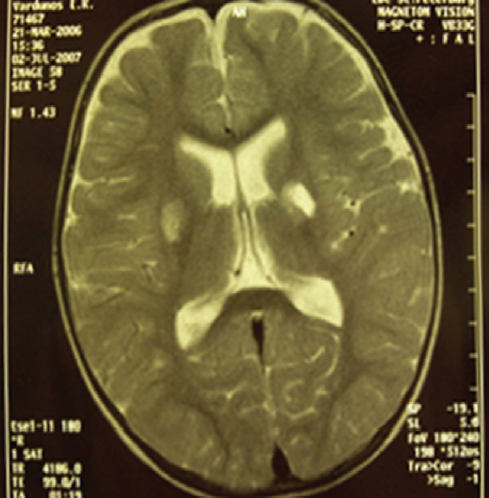

У 23 % детей с ГМ гемофильной и менигококковой этиологии выявлены очаги патологического МР-сигнала, обусловленного васкулитом с развитием множественных мелких зон ишемии различных размеров, округлой или овальной формы, с нечеткими контурами, которые локализовались как в субкортикальных, так и в перивентрикулярных отделах белого вещества (рис. 1).

Рис. 1. Магнитно-резонансная томограмма головного мозга ребенка, 1 год 9 мес. Диагноз: «Гнойный менингит гемофильной этиологии. Острое нарушение мозгового кровообращения по ишемическому типу в бассейне правой среднемозговой артерии». Режим Т2-ВИ. В базальных структурах справа определяется зона высокой интенсивности сигнала размерами 1,8 × 1,2 × 1,4 см с нечеткими контурами. В базальных отделах слева — лакунарная киста размерами 1,4 × 0,9 × 1,1 см / Fig. 1. MRI of a child, 1,9 years old. Diagnosis: Purulent meningitis of hemophilic etiology. Acute ischemic cerebral circulation disorder in the basin of the right middle cerebral artery. T2-VI mode. In the basal structures on the right, a zone of high signal intensity with dimensions of 1.8 × 1.2 × 1.4 cm with fuzzy contours is determined. In the basal regions on the left – a lacunar cyst measuring 1.4 × 0.9 × 1.1 cm